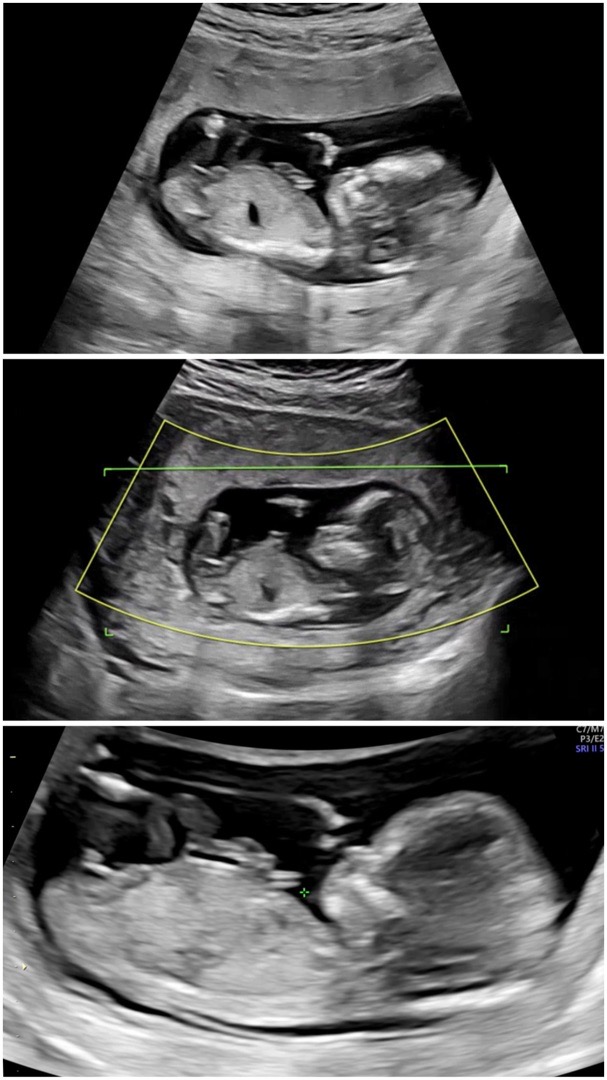

각도법 봐주세요!

각도법 봐주실 분 있을까요??

아들같아요!